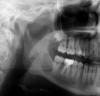

лина 14 Опубликовано 14 июля, 2009 Поделиться Опубликовано 14 июля, 2009 Недавно была у врача и ужаснулась. На снимке была обнаружена киста.Врач мне сказал,что с операцией лучше не медлить и лучше проводить осенью.Не могли бы рассказать по подробней, как проводятся такие операции?Может что-нибудь посоветуете,подскажите,а то страшновато. Заранее огромное спасибо. Ссылка на комментарий

Никсон Опубликовано 14 июля, 2009 Поделиться Опубликовано 14 июля, 2009 Недавно была у врача и ужаснулась. На снимке была обнаружена киста.Врач мне сказал,что с операцией лучше не медлить и лучше проводить осенью.Не могли бы рассказать по подробней, как проводятся такие операции?Может что-нибудь посоветуете,подскажите,а то страшновато. Заранее огромное спасибо. Операцию при таком местоположении кисты проводить лучше в стационаре, чем амбулаторно. В любом случае в операционной. Проводится открытая биопсия с обязательным иссечением костной ткани и оболочки ее кисты по типу цистотомии. Биопсия одновременно является первым этапом хирургического лечения кисты. Ссылка на комментарий

Никсон Опубликовано 15 июля, 2009 Поделиться Опубликовано 15 июля, 2009 Откуда такая киста могла появится? Если Вам не удаляли "зуб мудрости", то с большей долей вероятности, это примордиальная киста.Происходит она из-за нарушений в эмалевом органе в ранних стадиях развития зачатка зуба, до того как твердые ткани зуба начинают формироваться.Она как бы занимает место зуба - зуба нет, а киста есть. Ее необходимо оперировать в стационаре. Ну, желательно , в стационаре. Ссылка на комментарий

Olga Dgem Опубликовано 23 августа, 2009 Поделиться Опубликовано 23 августа, 2009 Обязательно исследование на КТ:форма,размер,близость к нижнечелюстному каналу.Анализ кисты в трёхмерном изображении позволит спланировать операцию и уменьшить риск осложнений.Обязательно заложите костеобразующее,чтобы не было перелома челюсти. Ссылка на комментарий